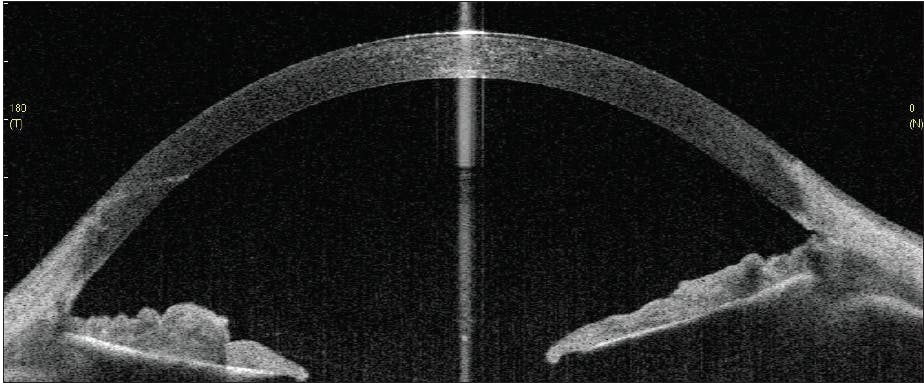

GATT was uneventful in both eyes. The IOP was stable in the midteens at postoperative week 6 without medication in the left eye. In the right eye, however, an IOP of 4 mm Hg and a slight relative shallowing of the anterior chamber on postoperative day 4 prompted further investigation. AS-OCT imaging with the Casia SS-1000 (Tomey) revealed a nasal cyclodialysis cleft spanning 39º of arc, with adjacent ciliochoroidal effusions measuring 623 μm in maximum height (Figure 2). Gonioscopic visualization was inadequate given the shallow anterior chamber and corneal striae on indentation due to hypotony.

Figure 2. On postoperative day 4, AS-OCT revealed a nasal cyclodialysis cleft spanning 39º of arc with adjacent ciliochoroidal effusions that had a maximum height of 623 µm.

Courtesy of Thomas A. Berk, MD, and Hady Saheb, MD, MPH, FRCSC